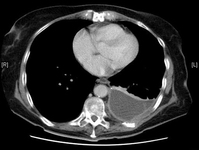

CT scan of thoracic empyema

From the collection of Najib Rahman, RTU, Oxford